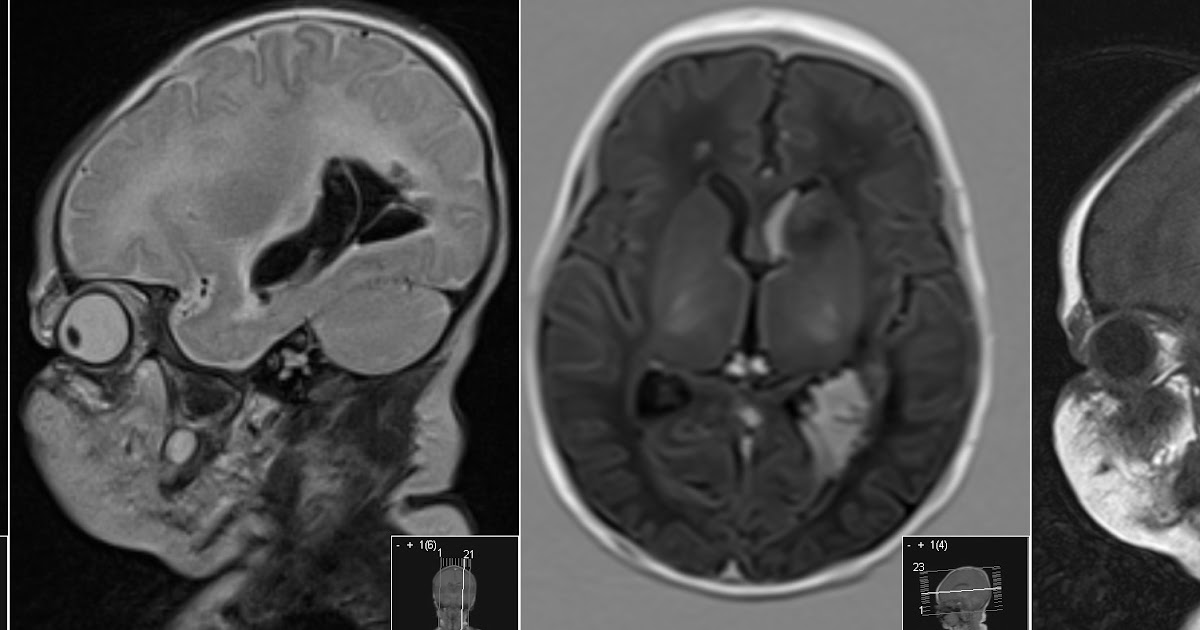

Brain lobes - annotated MRI | Radiology Case | Radiopaedia.org A case of advanced gastrointestinal stromal tumor (GIST)presenting with paraneoplastic syndrome. H. M. Guirgis et al., J Clin Oncol, 2004. Seizures and Radionecrosis From Non-Small-Cell Lung Cancer Presenting As Increased Fluorodeoxyglucose Uptake on Positron Emission Tomography. Patrick G. Morris et al., J Clin Oncol, 2011. Frontiers | 101 Labeled Brain Images and a Consistent Human Cortical ... Labeled anatomical subdivisions of the brain enable one to quantify and report brain imaging data within brain regions, which is routinely done for functional, diffusion, and structural magnetic resonance images (f/d/MRI) and positron emission tomography data. Brain MRI: How to read MRI brain scan | Kenhub MRI is the most sensitive imaging method when it comes to examining the structure of the brain and spinal cord. It works by exciting the tissue hydrogen protons, which in turn emit electromagnetic signals back to the MRI machine. The MRI machine detects their intensity and translates it into a gray-scale MRI image. The MRI Dataset with labels. | Download Scientific Diagram Download scientific diagram | The MRI Dataset with labels. from publication: Detection of brain abnormality by a novel Lu-Net deep neural CNN model from MR images | The identification and ...

Radiodiagnosis - Imaging is Amazing-Interesting cases: Phenytoin associated Cerebellar atrophy - MRI